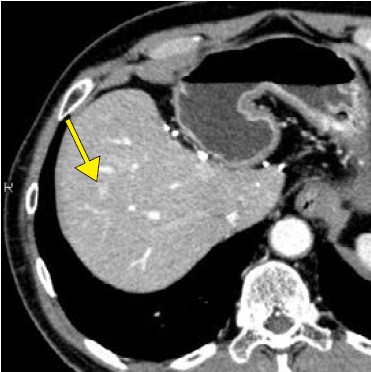

CLEAR Motionについては、CardiacとBodyの両方で使用している。稲垣係長は、「大動脈解離を疑い、従来であれば心電図同期が必要な症例でも、Aquilion ONE / INSIGHT Editionではガントリの回転速度やヘリカルスキャンも高速化していることに加えて、CLEAR Motionをかけることで心拍動によるアーチファクトを抑えて、ブレのない画像が得られます。スループットも向上しており、患者さんにとっても有用な検査が提供できます」と評価する。

CLEAR Motion OFF + Hybrid-IR CLEAR Motion OFF + Hybrid-IR

CLEAR Motion OFF + DLR CLEAR Motion OFF + DLR

CLEAR Motion ON + PIQE CLEAR Motion ON + PIQE

図2 原発性肺がん、肺転移症例で経過観察中

PIQE+ CLEAR Motionの併用で、心拍動に伴うアーチファクトを低減し、

高い時間分解能かつ高精細画像の両立が期待できる。